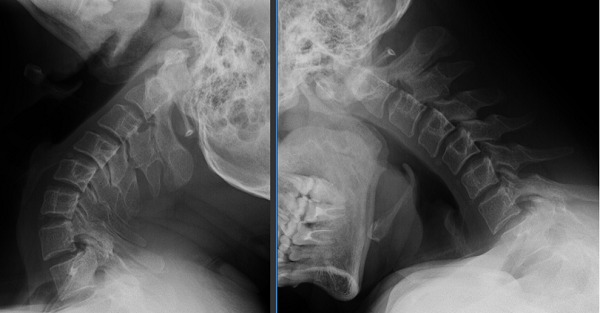

手术由柏涛主任医师、王国著副主任医师、董谐主治医师联手操刀,麻醉和护理团队全程精准护航,整个手术过程配合默契,术中失血量较少,最终圆满完成。麻醉苏醒后,贾先生意识清楚、对答切题、四肢活动正常。当看到贾先生能跟随手术医生的指导进行四肢的活动检查时,大家犹如面对强大的敌人打了一场胜仗,心中满是喜悦之情。

出院那天,贾先生脸上洋溢着久违的笑容:“之前那种随时昏昏沉沉、晕乎乎的感觉完全没有了,手也没有再麻过,感觉太好了。”对他而言,这场手术不仅解决了生理上的痛苦,更重拾了他继续美好生活的信心。而对他的家人来说,最让他们安心的,是家里的顶梁柱可以脱离疾病的折磨,继续为家人撑起一片天。

图片2

寰枢关节脱位,这种疾病隐匿性强,早期症状容易混淆,但若拖延不治,可能压迫神经血管,严重时甚至导致瘫痪、危及生命。此前,不少患者因当地医疗条件限制,不得不远赴外地求医。玉溪市人民医院骨外一科成功引入世界领先的由颅椎外科王超教授发明的手术技术,通过进修学习、王超教授亲临会诊手术、独立自主完成手术的路线,目前已为来自普洱、曲靖、楚雄及玉溪本地10余位患者成功开展了寰枢关节脱位手术。